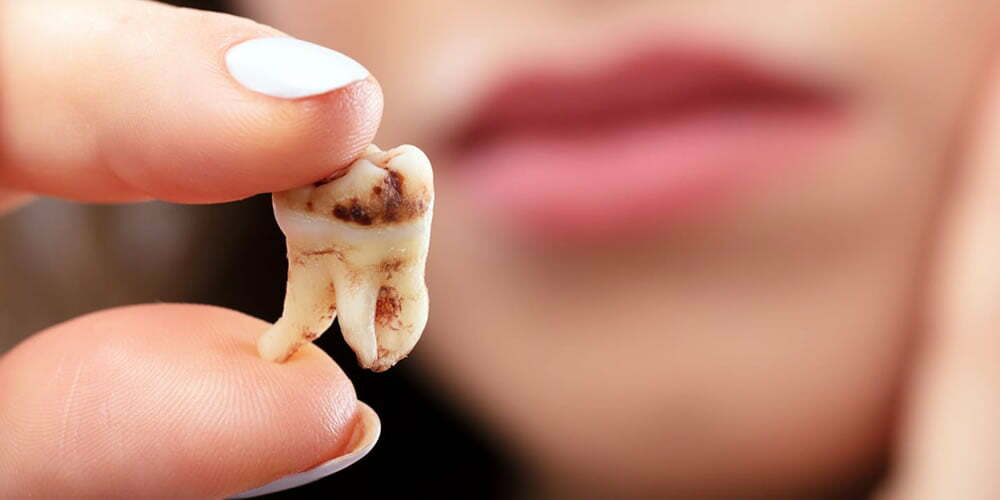

Lamina porselenlerin yapamayacağı şey – porselen laminaların sınırlamaları göz önüne alındığında, kötü diş pozisyonu, kök pozisyonunda büyük farklılıklar, yanlış ısırma ilişkileri ve kötü profil gibi tekniğin düzeltemeyeceği durumlar da vardır.